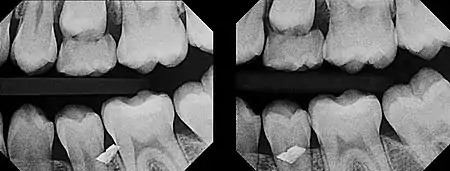

In 1909, Charles A. Clark described a radiographic procedure for localizing impacted teeth to determining their relative antero-posterior position.[1] If the two teeth (or, by extension, any two objects, such as a tooth and a foreign object) are located in front of one another relative to the x-ray beam, they will appear superimposed on one another on a dental radiograph, but it will be impossible to know which one is in front of the other. To determine which is in front and which is behind, Clark proposed his SLOB rule, as a complicated set of three radiographs, but which can be simplified as follows using just two:

- Expose another film while angle of the x-ray beam has been changed. If an object moves in the same direction as the source of the x-ray beam, it is lingual to the other object. If the object moves in the opposite direction of the source, it is buccal to the other object.

In 1952, Richards amended this rule using only 2 radiographs,[2][3] asserting that the object positioned more buccally will move more relative to the object positioned more palatally or lingually.